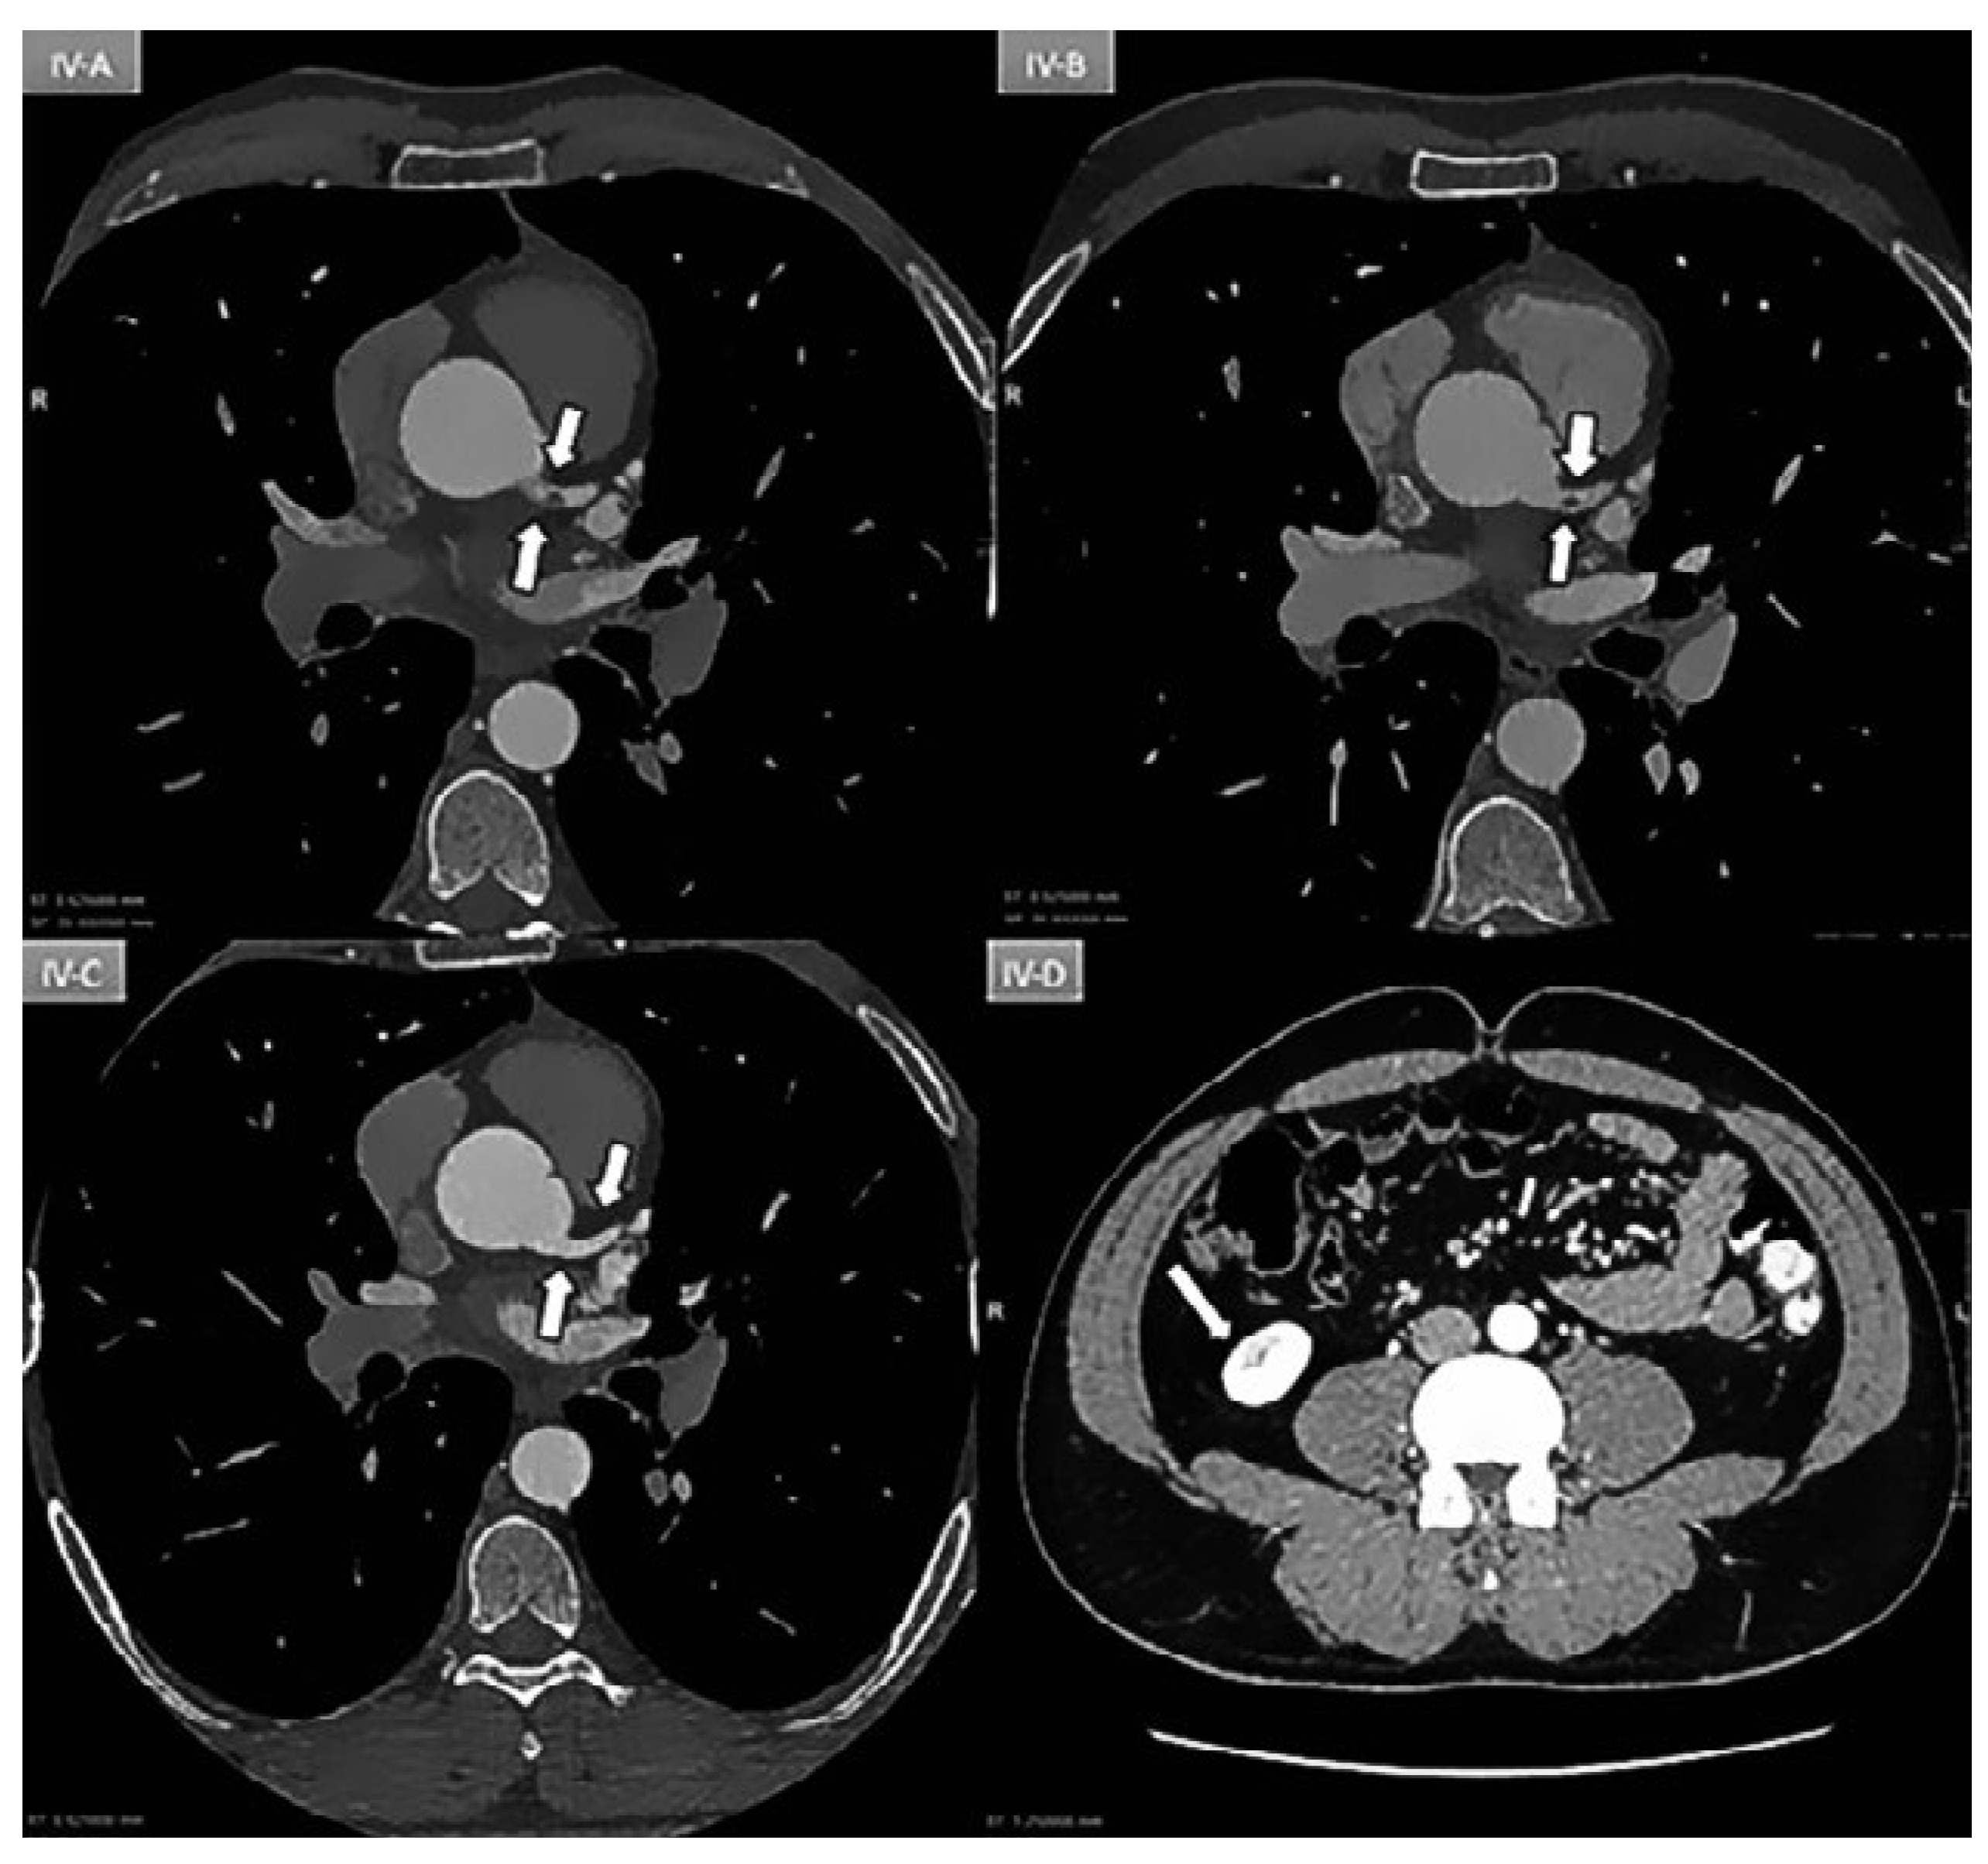

Myocardial Infarction due to Obstruction of the Left Main Coronary

Case report